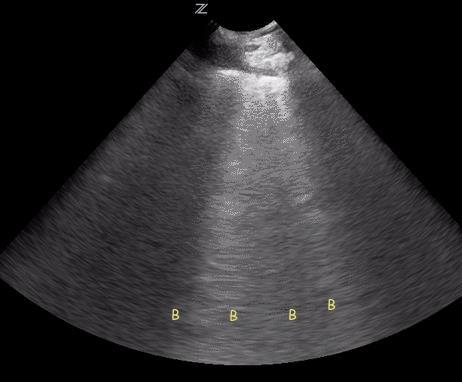

❑ Plan media or visual aids: Decide if whiteboard sketches, imaging reviews, or brief slide visuals will help reinforce key teaching points.

❑ Differential diagnosis

❑ Pathophysiology review